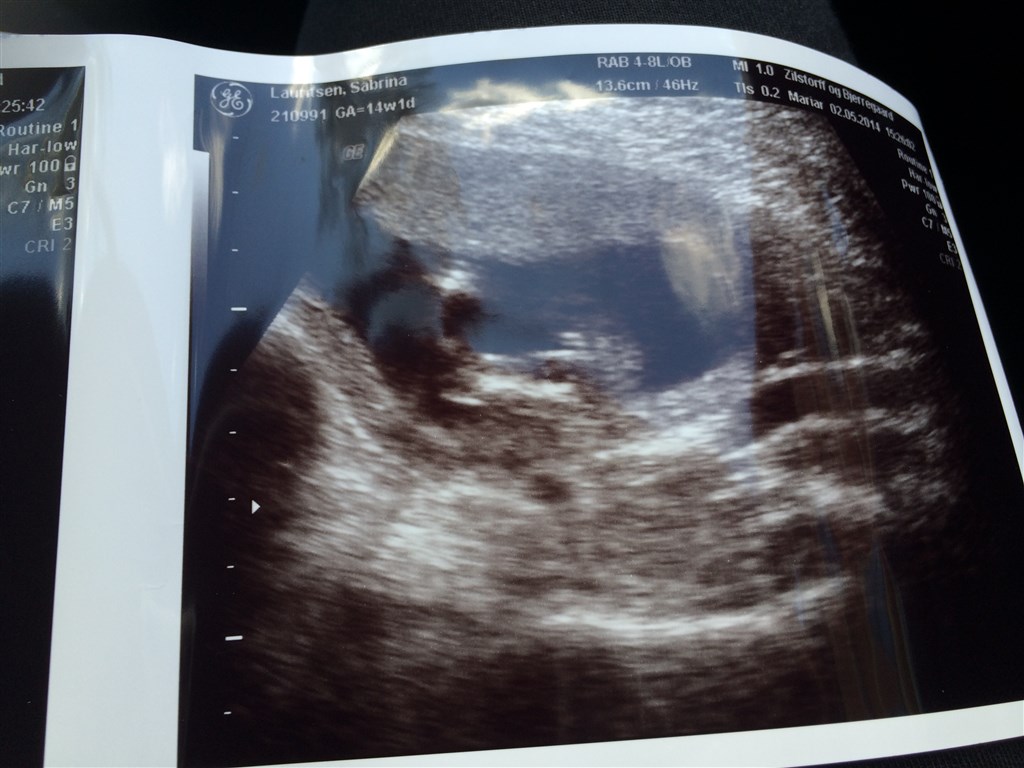

Jeg har lige været inde hos scanningskliniken på Østerbro, hvor jeg fik 99% sikkerhed på at jeg ..... Venter mig en lille pige!

Der var kun 1% for at der var en dreng, men jeg har selvfølgelig fået en ny tid for den sidste procent.. Men jeg kunne godt begynde stille og roligt at købe lyserøde ting :-)

Der står 14+1 på billederne

Nej, de fleste private klinikker garanterer fra 14+0